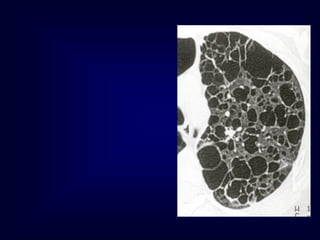

b. Reticular Pattern

A reticular pattern results from the summation

or superimposition of irregular linear

opacities.

The term reticular is defined as meshed, or in

the form of a network. Reticular opacities can be

described as fine, medium, or coarse, as the

width of the opacities increases.

A classic reticular pattern is seen with pulmonary fibrosis,

in which multiple curvilinear opacities form small

cystic spaces along the pleural margins and lung

bases (honeycomb lung)

This 50-year-old man presented with end-stage lung fibrosis

PA chest radiograph shows medium to coarse reticular

B: CT scan shows multiple small cysts (honeycombing) involving

predominantly the subpleural peripheral regions of lung. Traction

bronchiectasis, another sign of end-stage lung fibrosis.